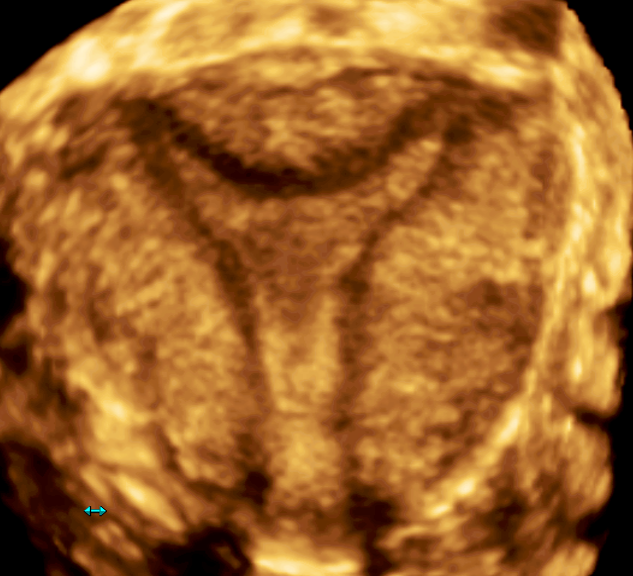

Современные экспертные УЗИ сканеры дают возможность проводить исследования всех органов в 3D. Это позволяет, используя полученный массив данных, получать диагностические сечения в любой плоскости, недоступной для обычного 2D УЗИ. Наиболее интересной является фронтальная. Например, визуализация полости матки. Диагностическая возможность выявления пороков развития превосходит все другие методы (рентгеновские и МРТ). Метод также позволяет уточнить положение ВМК (спирали) в полости матки, расположение миоматозных узлов, расположение плодного яйца на малых сроках, полипов. Сегодня современное экспертное ультразвуковое исследование невозможно без использования 3D УЗИ.